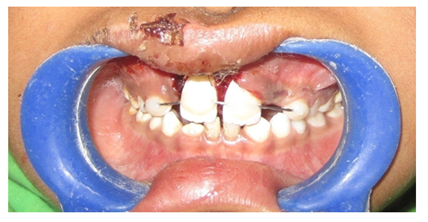

A 10year old boy reported to the department of Pedodontics with a chief complaint of missing upper front tooth and gave a history of fall from bike while 5 days back. They had been to pediatrician for the lacerated lip and got it sutured. Parents had kept the avulsed tooth in paper without knowledge of reimplantation of the same tooth. Patient had no relevant medical and family history. On examination swelling and suture was present on upper lip, lacerated gingiva with healing socket in 11 regions. 21 was intact, vital and non mobile. (Figure 1) (Figure 2) On examination of avulsed tooth 11, it was found to have open apex (Figure 3). On intraoral radiographic examination, no fracture was seen with alveolar bone (Figure 4). Thus avulsed tooth was cleaned and debrided with soft pumice prophylaxis, gentle scaling was done to remove ligament remnants. It was then placed in 1.23% sodium fluoride for 15minutes. Extraoral endodontic therapy was also done using retrograde filling of MTA (Figure 5). Local anesthesia was administered and socket was cleaned, curetted and irrigated to remove clot and debris and 11 was slowly reimplanted in socket. Orthodontic wire – composite splinting was done for 4weeks as the dry storage was more than 60minutes (Figure 6). Systemic antibiotics amoxicillin and doxycycline were prescribed for 5days. The patient was recalled after 1 month and splint was removed. No mobility was present. Again patient was recalled after 2months to check the condition (Figure 7). Again patient was recalled after 6months; tooth had slightly discolored but was not mobile and maintained the space (Figure 8). Patient was happy and contended with the reimplantation of his own tooth without disturbing his original look.

Figure 6 Intraoperative photograph showing splinting.